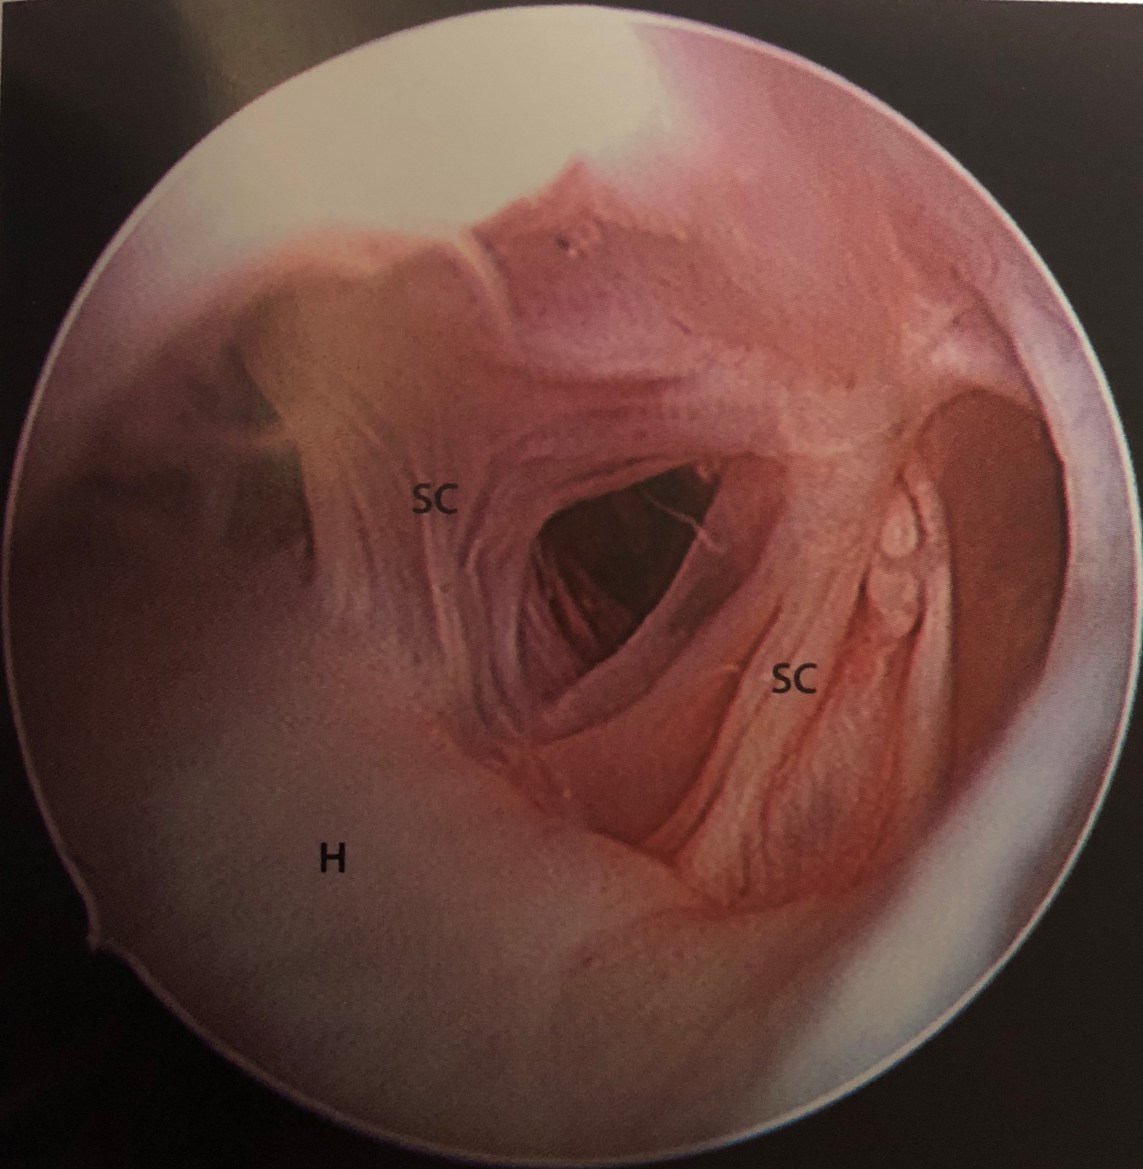

Upload Date: January 23, 2019 Full Size Image Dimensions: 2292 × 2346 Image Parent Post: ΑΡΘΡΟΣΚΟΠΗΣΗ ΑΓΚΩΝΑ

Α.Δυσκαμψία αγκώνα-Συμφυσιόλυση